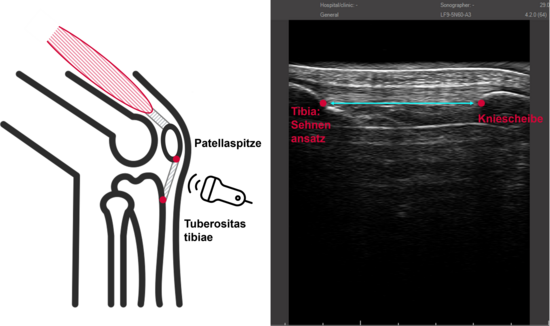

Wir nutzen Ultraschall, um die Muskeln und Sehnen zu untersuchen. Mit dynamischem Ultraschall messen wir die Muskelarchitektur während einer Kontraktion, z. B. Länge und Ausrichtung der Muskelfasern. Zusätzlich wird die Steifigkeit der Patellarsehne erfasst, um die Kraftübertragung von Muskel zu Knochen zu beurteilen.